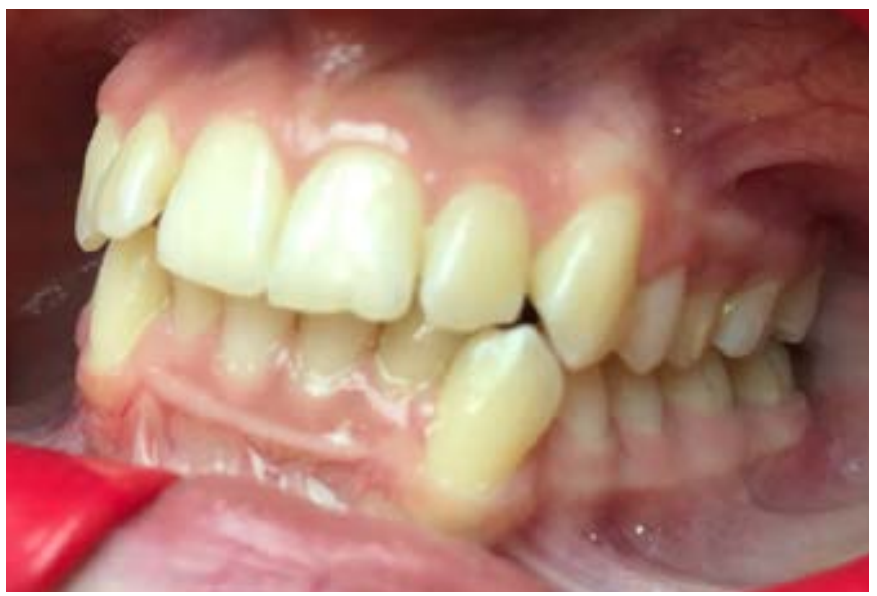

Первые признаки РД проявляются при сменном прикусе на этапе прорезывания постоянных резцов, чаще на нижней челюсти (рис. 1).

Рис. 1. До ортодонтического лечения: рецессия в области зуба 3.1